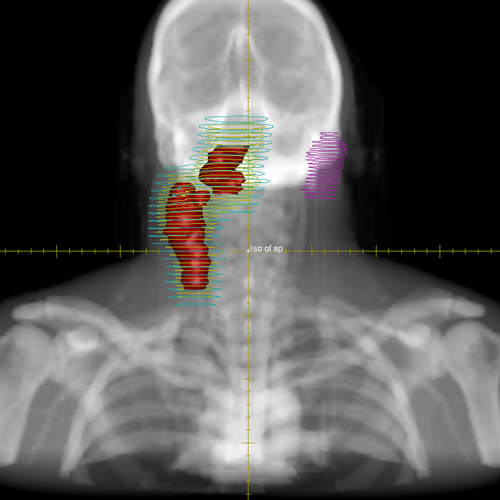

Module 3 Test Image 1

The red shaded area identifies which of the following?